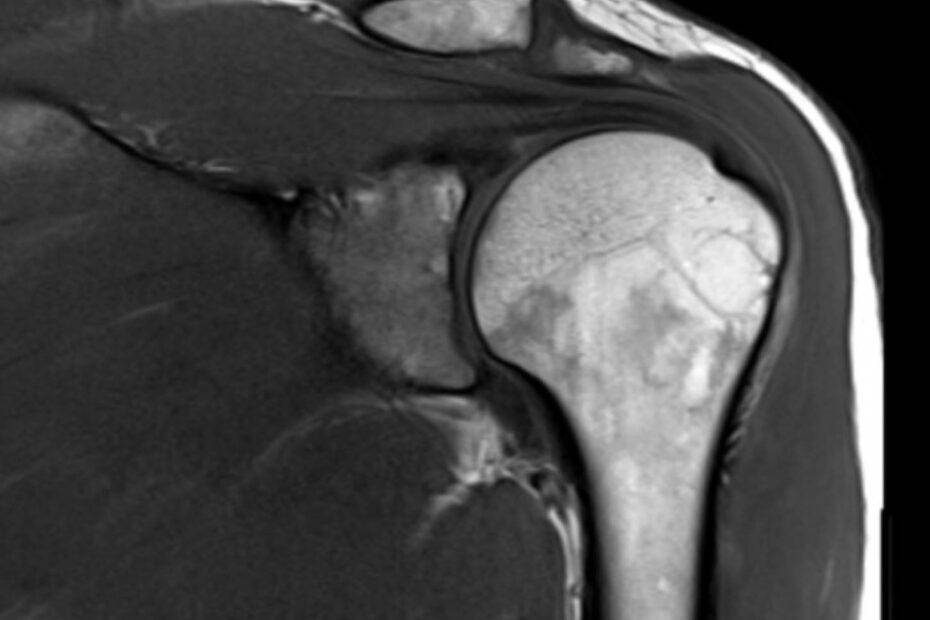

Die Magnetresonanztomographie der Schulter, kurz MRT Schulter genannt, ist eine bildgebende Untersuchung, die detaillierte MRT Bilder der Schulterstrukturen liefert, ohne Röntgenstrahlen zu verwenden. Sie ermöglicht die präzise Diagnose von Schulterschmerzen, Verletzungen, Arthrose und weiteren Erkrankungen der Schulter. Was ist eine MRT Schulter? Eine Magnetresonanztomographie (MRT) oder auch Kernspintomographie der Schulter ist eine schmerzlose bildgebende Untersuchung, … MRT Schulter weiterlesen